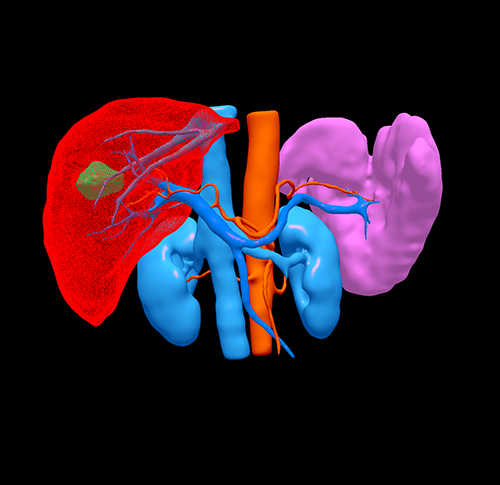

S7肝癌 门脉高压脾亢---S7切除 贲门周围血管离断